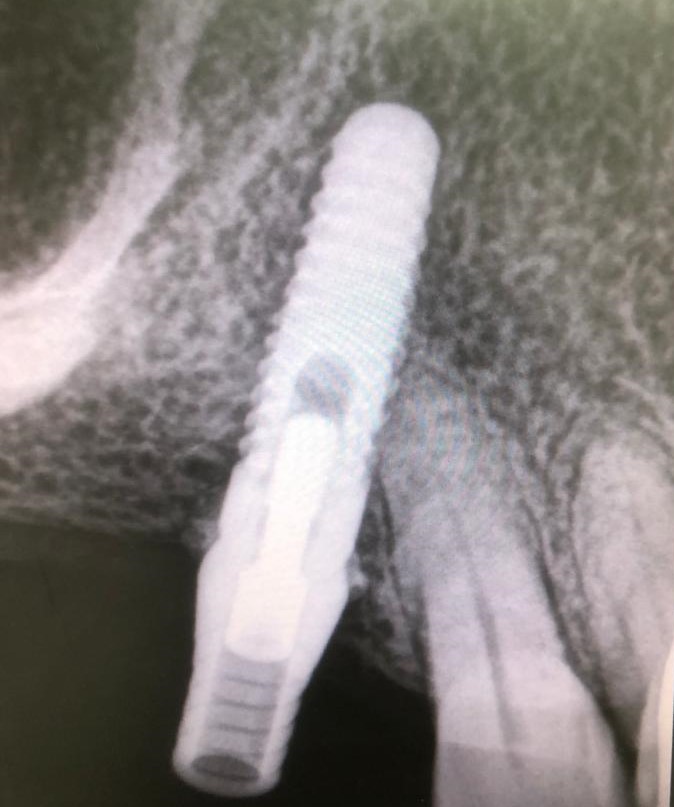

Exponemos nuevo caso de paciente con una fractura del tornillo pasante sobre un implante unitario molar. El tornillo pasante es la parte fundamental de la conexión y es el que está roto dentro y gripado, de tal forma que no pudimos extraer con el aparato de ultrasonido.

Como hemos comentado es un molar, es decir, una pieza dental en la zona posterior de la boca y con una posición del implante muy inclinada para poder esquivar el seno maxilar, lo cual dificulta mucho el trabajo.